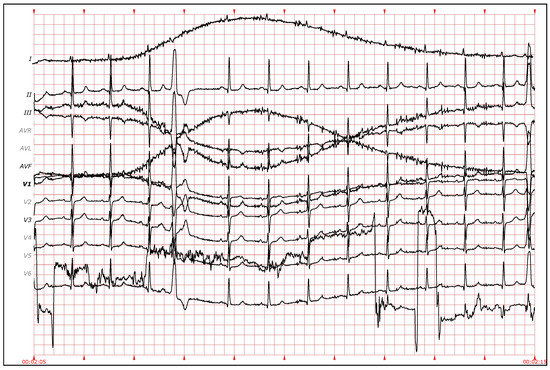

There are some types of arrhythmia, like premature atrial contractions and atrioventricular, or fusion and escape beats, in which the morphology of the QRS complexes is similar. Therefore, it is not feasible to distinguish between them using just QRS morphology information (see Figure 8 and Figure 9). The P wave does provide relevant information in these cases, but the difficulty in identifying it, especially in ambulatory ECG, often leads to attempts to obtain similar information from the distance between heartbeats [13,42]. Therefore, to allow the clustering algorithm to distinguish between different types of heartbeats with similar QRS morphology, two features based on the distance between heartbeats ( and ) were added as follows:

Figure 8.

Electrocardiogram (ECG) fragment with several normal beats at the beginning. Around the middle of the fragment, the distances between the heartbeats increase and escape beats appear. (Source: MIT-BIH Arrhythmia Database, recording 222, from 0:12:36 to 0:12:46).